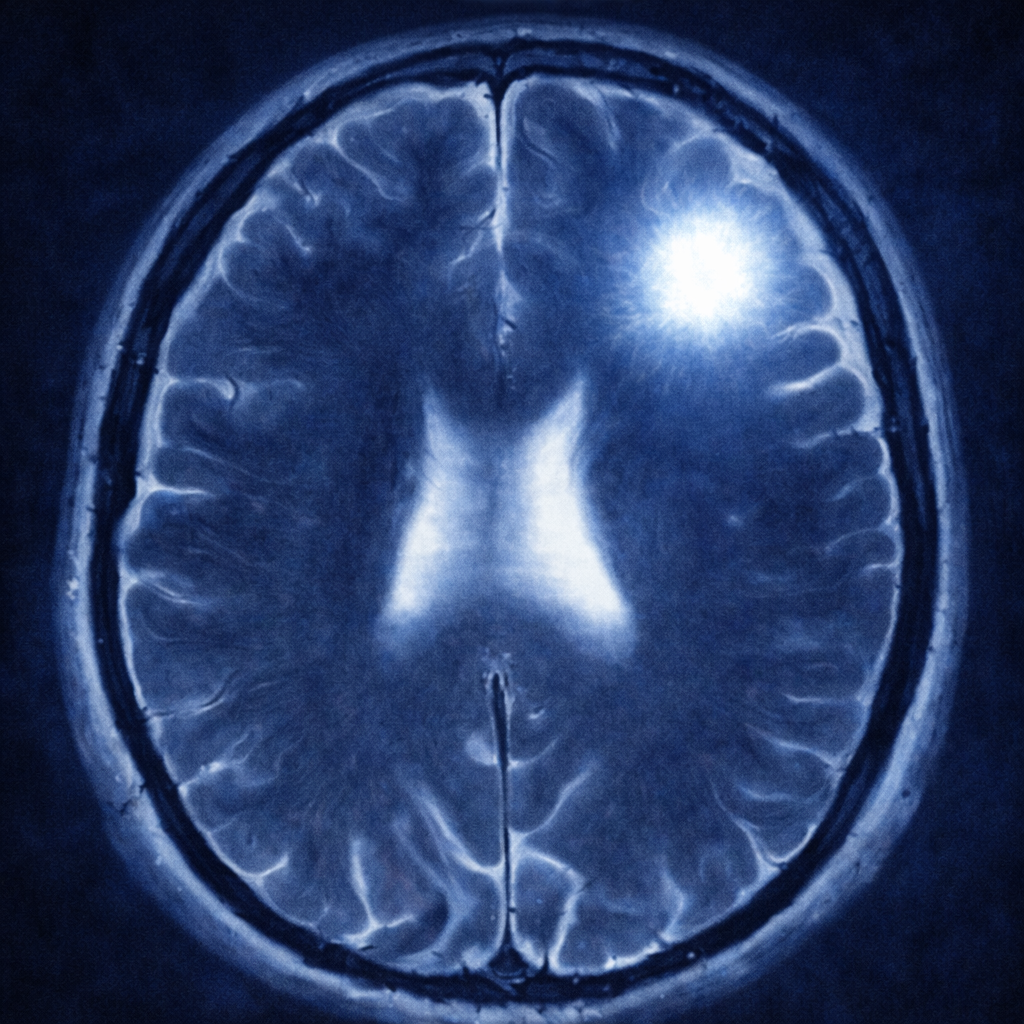

La resonancia magnética es el estudio inicial para la evaluación preoperatoria de un astrocitoma. Este estudio podrá analizar tanto la localización como las características del tumor. Dentro de las características más importantes están evaluar si capta o no el medio de contraste y qué tanta inflamación produce en los tejidos vecinos. Sin embargo, el diagnóstico definitivo de un astrocitoma se da, únicamente, a través de una biopsia con un análisis histopatológico, inmunohistoquímico y molecular. Es decir, el diagnóstico se puede establecer solamente con cirugía.